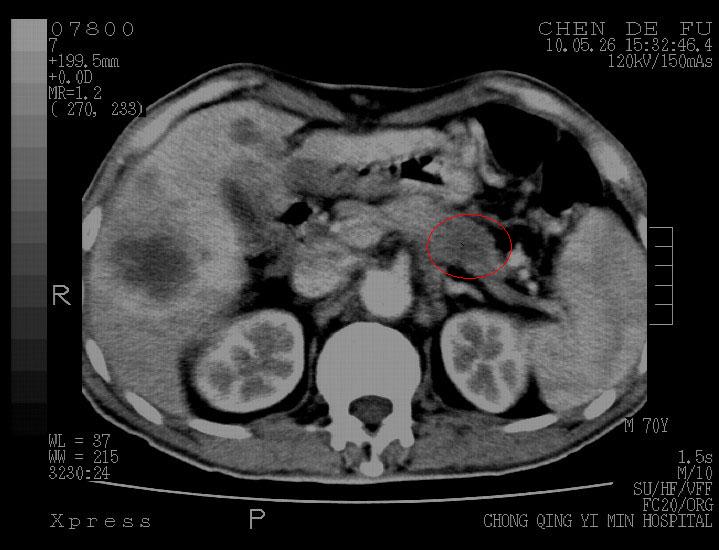

性别 男 70岁  因上腹部不适半月余,全身皮肤黄染来院检查。

考虑胰腺癌并肝脏多发性转移。

肝内多发结节状低密度影,边缘欠清,增强表现为快进快出,符合肝癌表现,需与转移鉴别。脾内不均匀强化不一定是转移。另有胆囊炎、左肾结石

符合胰腺癌肝脏转移